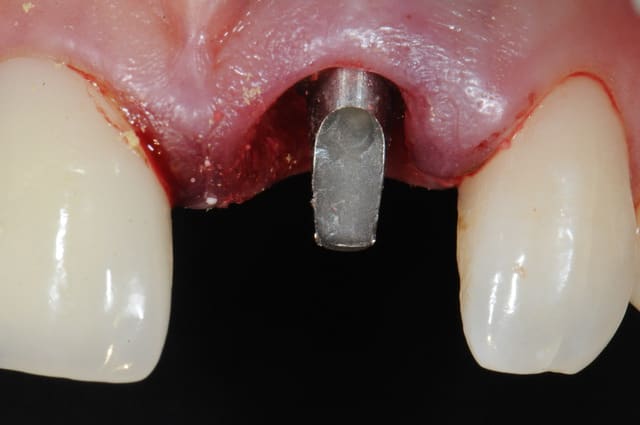

1 implantation

je n'étais pas du tout sure de le mettre car je n'avais qu'à peine 3à4 mm d'ancrage en apical.

je me suis fais un peu violence pour essayer tout de même quitte à perdre l'implant.

j'ai surtout été très surpris par l'excellente stabilité primaire malgré le peu d'os.

2 -3-4 implant et pilier en place

séquence prothèse:

1-2-3 élaboration de la provisoire sur le pilier définitif et vérification des contacts occlusaux

4-5- pilier titane angulé à 7° et comblement du hiatus avec du Bioos-collagene qui supporte beaucoup mieux l'exposition que le Bioos simple

6-7-8 ayéh! j'ai fini pour aujourd'hui.

Salut Thomas, tu as placé le pilier définitif le jour de la pose, tu fais comment après pour l'empreinte ? Est-ce qu'il y a un système d'empreinte sur pilier pour ces piliers là ?

pilier définitif oui, mais pas serrage définitif...

je me reserve le droit de changer si la hauteur que j'ai estimé ne me convient pas.

l'idéal est de trouver dès la mise en esthétique immédiate le bon pilier pour ne plus avoir à le démonter